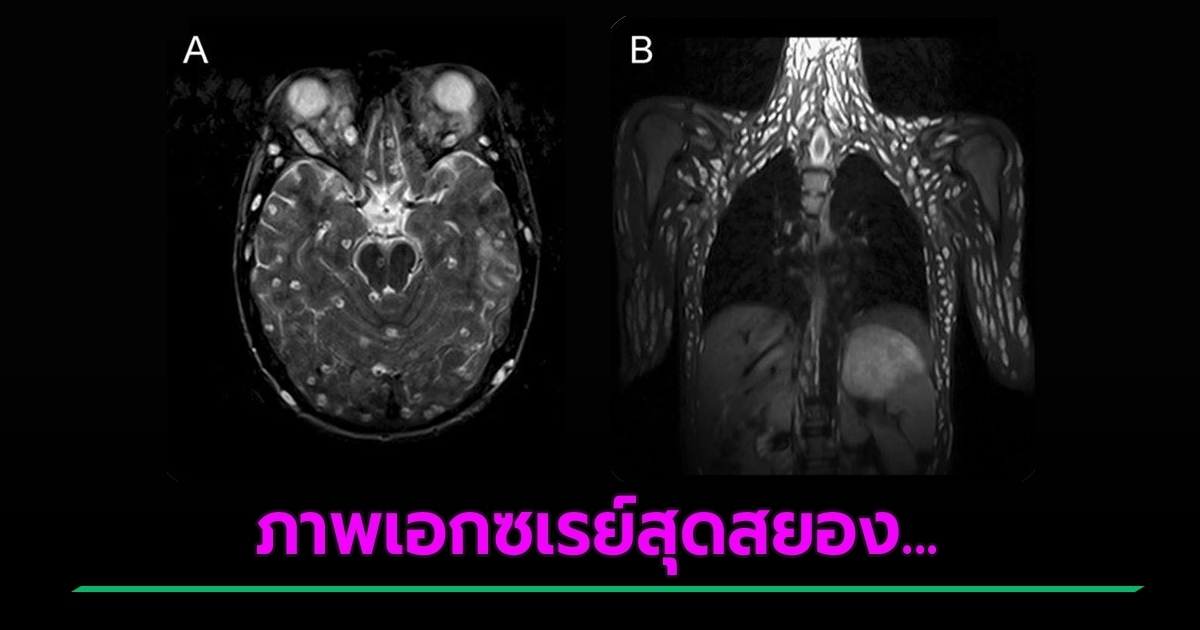

เผยภาพเอกซเรย์พยาธิตืดหมูเพียบ กระจายทั่วร่างกาย หลังวัยรุ่นอายุ 18 ปวดหัวรุนแรง และชัก มารักษาที่โรงพยาบาล คาดเกิดจากการกินน้ำ ผักผลไม้ ปนเปื้อนไข่พยาธิ

วันที่ 12 มิถุนายน 2563 เฟซบุ๊ก PDRC ศูนย์วิจัยโรคปรสิต สำนักวิชาแพทยศาสตร์ มหาวิทยาลัยเทคโนโลยีสุรนารี เผยภาพเอกซเรย์สุดสยอง ของพยาธิตืดหมูในระยะตัวอ่อน (cysticercus) เป็นจุดขาว ๆ กระจายอยู่เต็มตัวของคนไข้ หลังจากที่คนไข้อายุ 18 ปีรายหนึ่ง เข้ามารักษาด้วยอาการ ปวดศีรษะอาเจียน ชัก และประสาทสัมผัสที่เปลี่ยนแปลง แพทย์จึงได้ทำการตรวจ MRI พบซีสต์พยาธิตืดหมูจำนวนมากในเนื้อเยื่อสมอง ศีรษะ กล้ามเนื้อ คอ ผนังหน้าอก ผนังหน้าท้อง, กล้ามเนื้อ 2 ข้างของกระดูกสันหลัง, สะโพก, กระดูกเชิงกราน และกล้ามเนื้อแขนขา